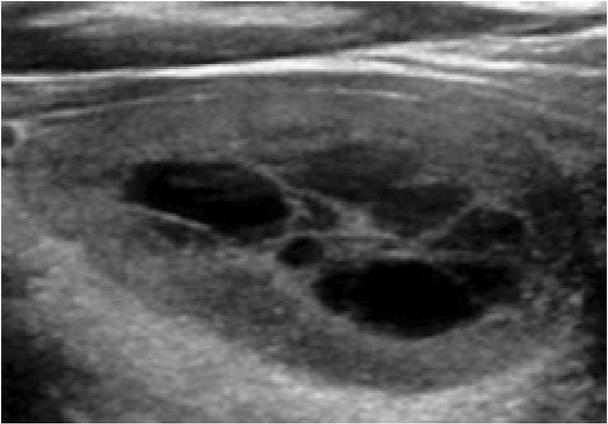

The echogenicity of a mixed cystic and solid nodule should be evaluated based on the appearance of its solid component alone (Fig. 3). An anechoic appearance (+0 points) is therefore not an option, as this feature is synonymous with a cystic consistency. It is also important not to misinterpret debris/blood clot/necrotic tissue in a cyst for viable solid material(4). Doppler US, careful interrogation of the cine clips, and appropriate adjustment of technical parameters (e.g. gain, depth, focal zone, frequency and dynamic range) may help in making this distinction(4).

Fig. 3

Greyscale sonographic image of a mixed cystic and solid nodule scored as ‘hypoechoic’ based on the echogenicity of the solid component